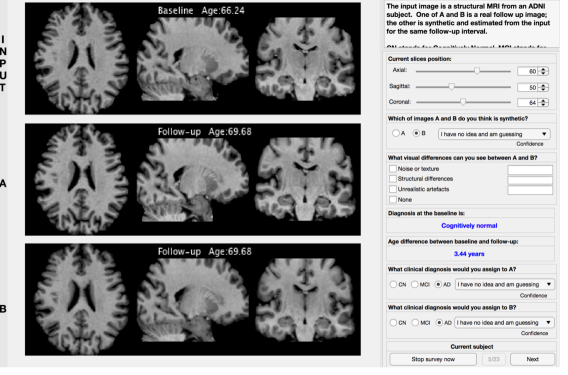

5.4 Radiological Assessment of Visual Perception and Disease Stage

Finally, expert image readers evaluated simulated images against real images in terms of perceived visual artefacts as well as diagnostic accuracy.

To do so, we performed a survey where we recruited 21 participants (4 neurologists, 4 neuro-radiologists, 10 neuroimaging experts and 3 medical imaging researchers with an average of 9 years experience), and we asked them to evaluate 22 randomly selected cases extracted from the test set. From these cases, 3 out of 22 subjects have progressed in a different diagnosis during the follow-up scan whereas the remaining 19 subjects have maintained the initial diagnosis.

We set up an online web application (see Fig. 7) that shows, for each of the 22 cases, a T1-weighted brain MRI of a patient. Below this MRI scan, two more images labelled A and B shown in random order to avoid any selection bias. One of these 2 images is the real follow up MRI of the same initial subject; the other is the synthetic image generated starting from the initial MRI and obtained for the same follow-up interval. Each participant is asked to identify the simulated image in each of these 22 cases.

Additionally, during the survey, the participants were asked to identify and classify possible visual differences selected from 2 severity scores (minor and major) and 3 different categories (noise/texture, structural differences and unrealistic artefacts) and to assign a clinical diagnosis to both A and B in order to verify that there is no clinical inconsistency between real and synthetic images. The age and diagnosis at the baseline scan and the age at the follow-up scan were displayed to help the participants to assign the correct diagnosis. Finally, for each case and each different task in the survey, the participants were asked to provide a confidence score selected from the following list:

-

•

None: ’I have no idea and am guessing’

-

•

Low: ’I have low confidence’

-

•

Medium: ’I am reasonably confident’

-

•

High: ’I am absolutely sure’

The results of this survey are presented in Fig. 8 where each task is represented with a different colour: i) bars in grey depict the results related to the discrimination task (real vs simulated images), ii) bars in orange depict the results related to the diagnosis using simulated images and iii) bars in blue depict the results related to the diagnosis using real images.